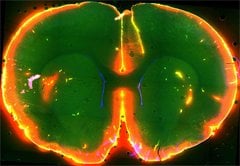

Scientists watched dye flow through the glymphatic system, a brain “plumbing” system, of a mouse when it was asleep (left) and then, later, when it was awake (right). More dye flowed into the brain during sleep. Results from this study suggest the brain may flush out toxic molecules associated with neurodegenerative disorders during sleep.

Image Source: The image is credited to Nedergaard Lab, University of Rochester Medical Center, and is adapted from the NIH/NINDS press release.